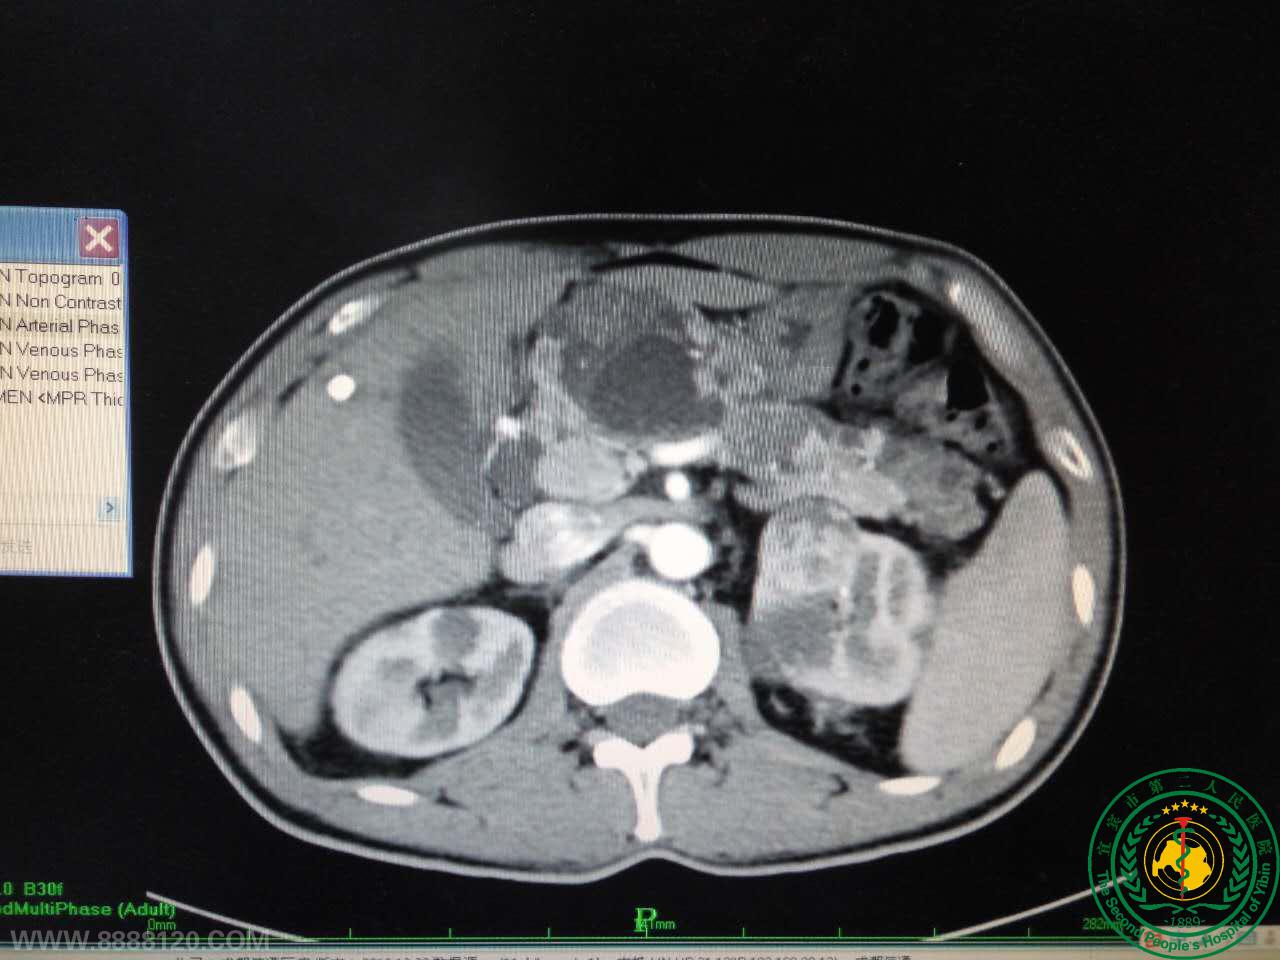

我科完成一例肾多发复杂肿瘤切除术

我科完成一例肾多发复杂肿瘤切除术13768